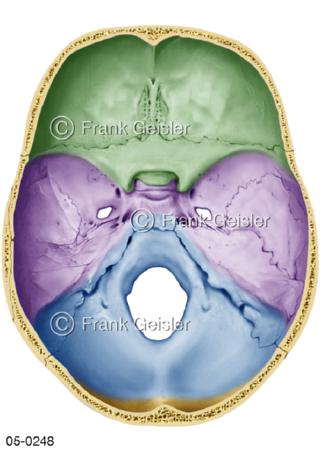

Bildergalerie Skelettsystem

Bilder zum Skelettsystem zeigen die Stützstruktur des menschlichen Körpers, die Knochen, eine besonders harte Form des Bindegewebes und Stützgewebes, welche das menschliche Skelett bildet, die Knochen des Stammes, der Extremitäten sowie der Gelenke